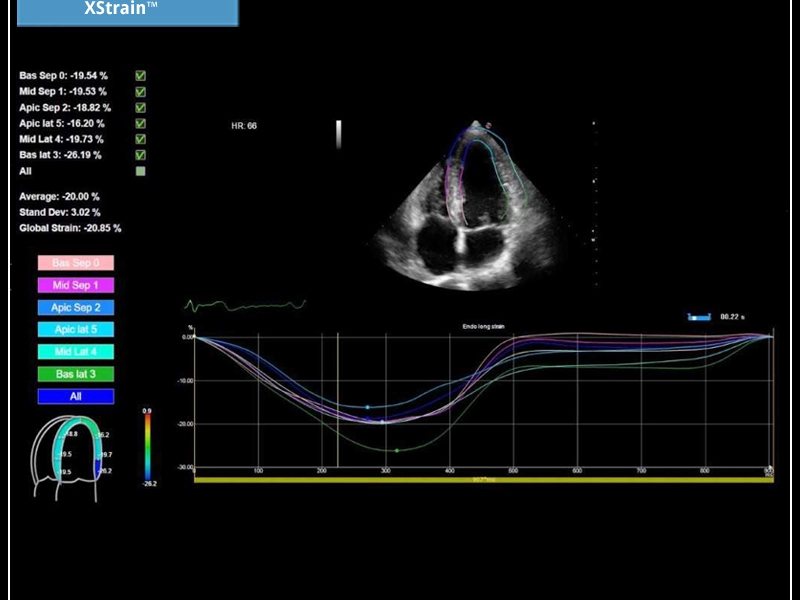

MyLab™X5 is equipped with comprehensive cardiac and vascular configurations. It functions as a complete system for ultrasound cardiovascular examination, and features customizable measurements and reporting.

General Imaging Cardiovascular